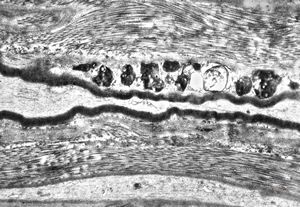

M, 2y. | globoid leukodystrophy (Krabbe disease) … n. suralis

M, 17y. | sea-blue histiocyte syndrome - kidney